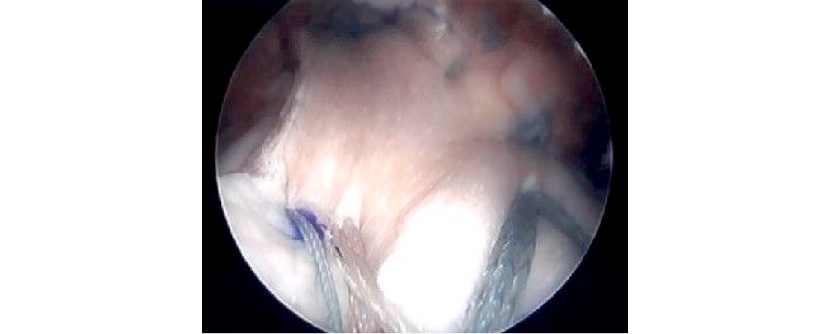

Arthroscopic revision rotator cuff repair

Arthroscopic images of a revision rotator cuff repair using patch augmentation to help with healing.

A) Initial camera image of tear after preparation.

B) Standard repair of the recurrent rotator cuff tear.

C) Four additional anchors placed around the repair to hold down the graft.

D) Final image after graft has been tied down securely over the traditional rotator cuff repair.